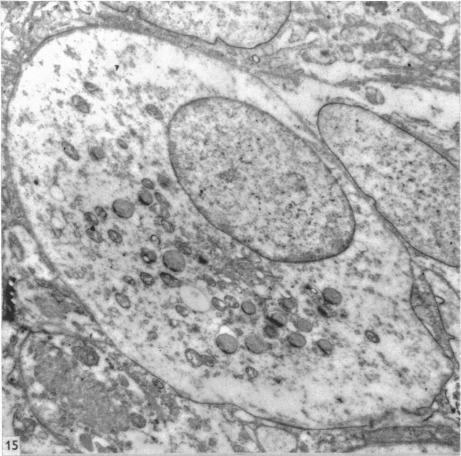

The cytology, histochemistry and electron microscopy of the granular cells of the metrial gland of the gravid rat.

J Anat. 1957 Jan;91(1):130-40.